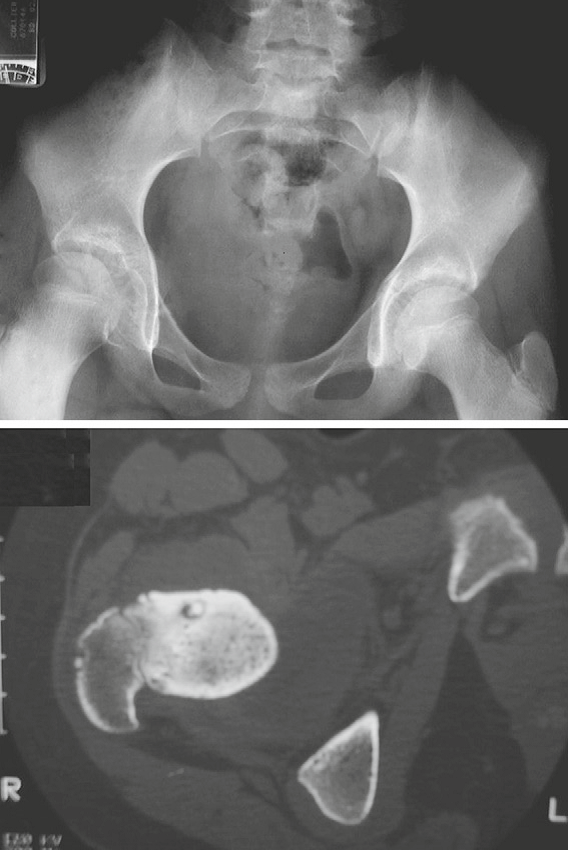

Osteoid osteoma in an 11-year-old girl.

A, Radiograph shows increased sclerosis of intertrochanteric

region of the right femur. Within this area of sclerosis is a

round central lucency (arrows) containing a central punctate

density.

There is associated joint effusion identified by asymmetric

widening of the right joint space (arrowheads).

B, CT scan shows dense nidus (arrow) within central lucency and surrounding sclerosis.